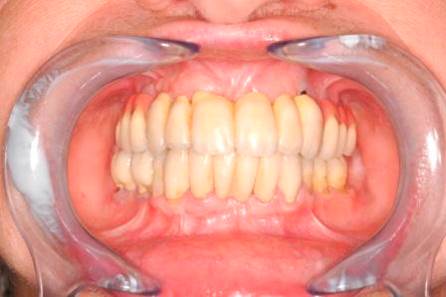

S pomocí zubních implantátů můžeme díky různým kotevním systémům (třmeny, kulové hlavy, Locatory) zajistit stabilitu a držení protézy nebo při použití většího počtu implantátů zhotovit pevné náhrady – můstky nalepené nebo našroubované na pevno na implantáty.

S těmito typy náhrad můžeme dosáhnout perfektní funkci, výbornou estetiku, fonetiku a současně zajistit u pacienta možnost dobré hygienickou péče a čištění, která je pro životnost implantátů velice důležitá.